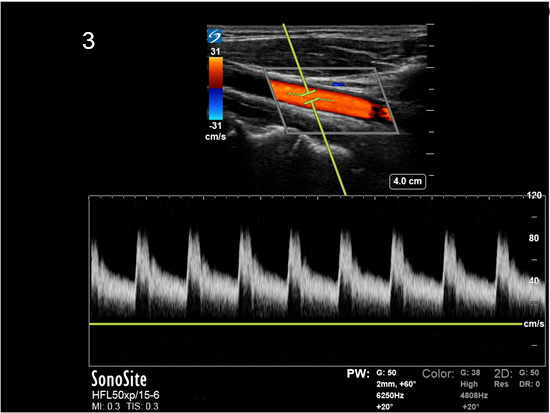

Instrumentation Sweep Speed Fast Image